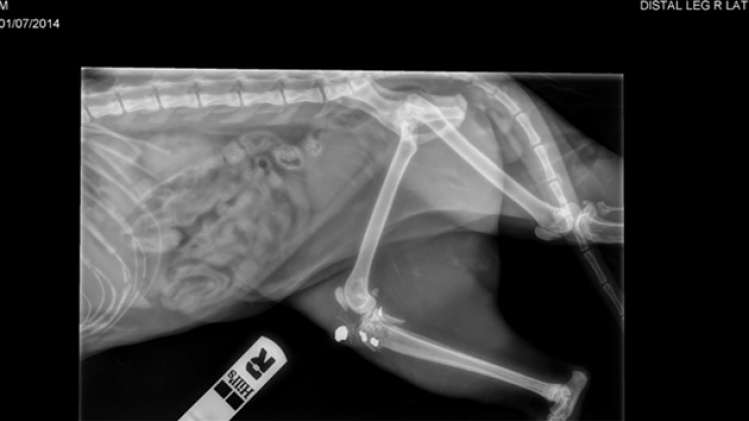

Les clichés issus de la radio passée à la clinique affichent l'impact de la balle. La suite des événements est particulièrement douloureuse pour sa propriétaire.

"Il a été touché au niveau de la cuisse. On ne pouvait pas mettre de visse ou de plaque. L’articulation avait explosé. La balle a été récupérée", précise-t-elle.